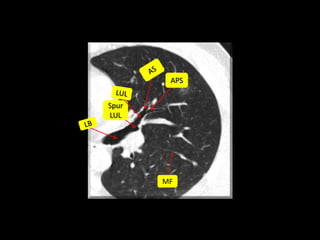

MF

Quiz

Ground-glass opacity at the level of the left upper lobar

bronchus

A. Apical Posterior

Segment

B. Anterior Segment

C. Lingula Superior

D. Lingula Inferior

66 http://radiographics.rsna.org/content/27/2/391/F27.expansion.html

Spur

LUL

APS